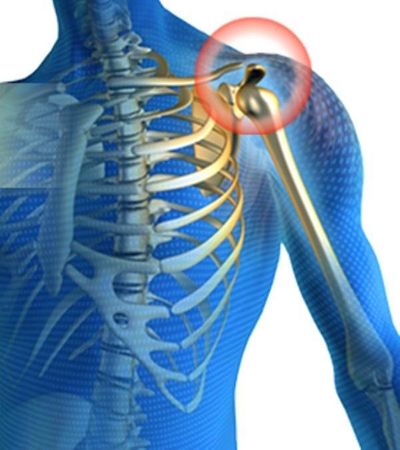

В нормальном состоянии суставные поверхности плечевого сочленения (головки плечевой кости и суставной впадины лопатки) покрыты гиалиновым хрящом – по характеристикам он плотный, упругий и гладкий. Благодаря этому головка кости легко скользит во впадине во время движения верхней конечности. При развитии некроза и образовании суставной мыши такая механика нарушается.

При рассекающем остеохондрите плечевого сустава возникают следующие нарушения. Со стороны сосудов, которые питают хрящевое покрытие головки плечевой кости (чаще) или суставной впадины лопатки (реже) наблюдаются патологические изменения – тромбоз (закупорка кровяным сгустком) и спазм сосудистой стенки (как реакция на присутствие в просвете тромба). В результате этого местное кровообращение страдает, в тканям поступает меньше кислорода и питательных веществ, что классически приводит к омертвению участка хряща. Образуется зона асептического некроза, которая имеет вид ограниченного очага. Омертвевший участок хряща некоторое время еще соединен со здоровыми хрящевыми тканями, но по мере развития деструктивных процессов он отламывается и оказывается в суставной поверхности.